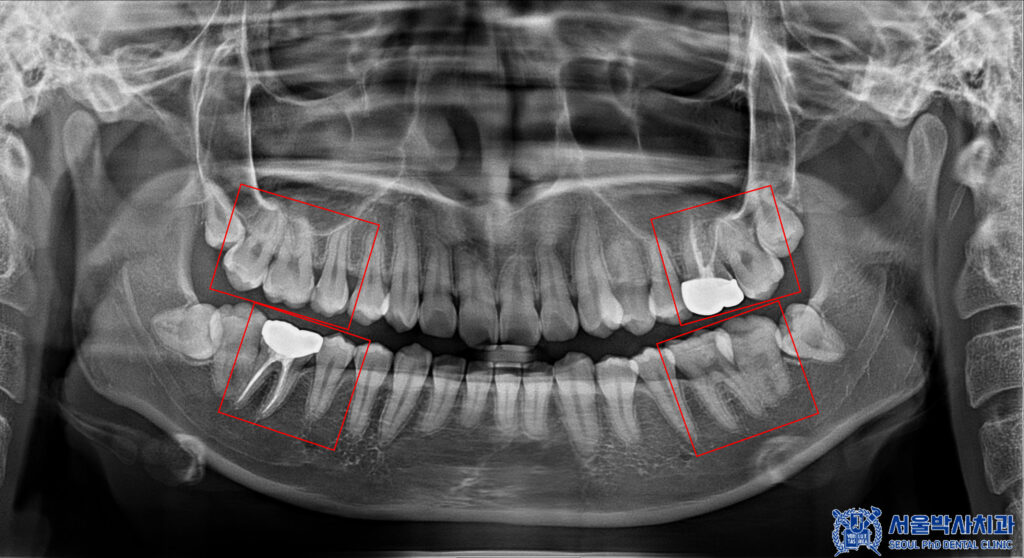

자세히 확인을 해보기 위해

파노라마를 촬영해 보았습니다.

파노라마 상에서도

다수 우식이 발견되었습니다.

신흥동치과 서울박사는

자연치아를 살리는 방향으로 진단하고

또 꼭 필요한 진료만 권해드리고자

충치가 깊지 않은 곳은 레진이나 인레이로,

충치가 깊은 곳은 신경치료 및 크라운으로

자연치아 보존 방향으로 치료를 계획하였습니다.